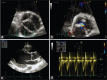

Figure 2

Transthoracic echocardiography in uncomplicated type 1 BAV. Aortic short-axis view (a), mild aortic regurgitation (b), normal ascending aorta diameters (c), and absence of significant aortic stenosis (d)